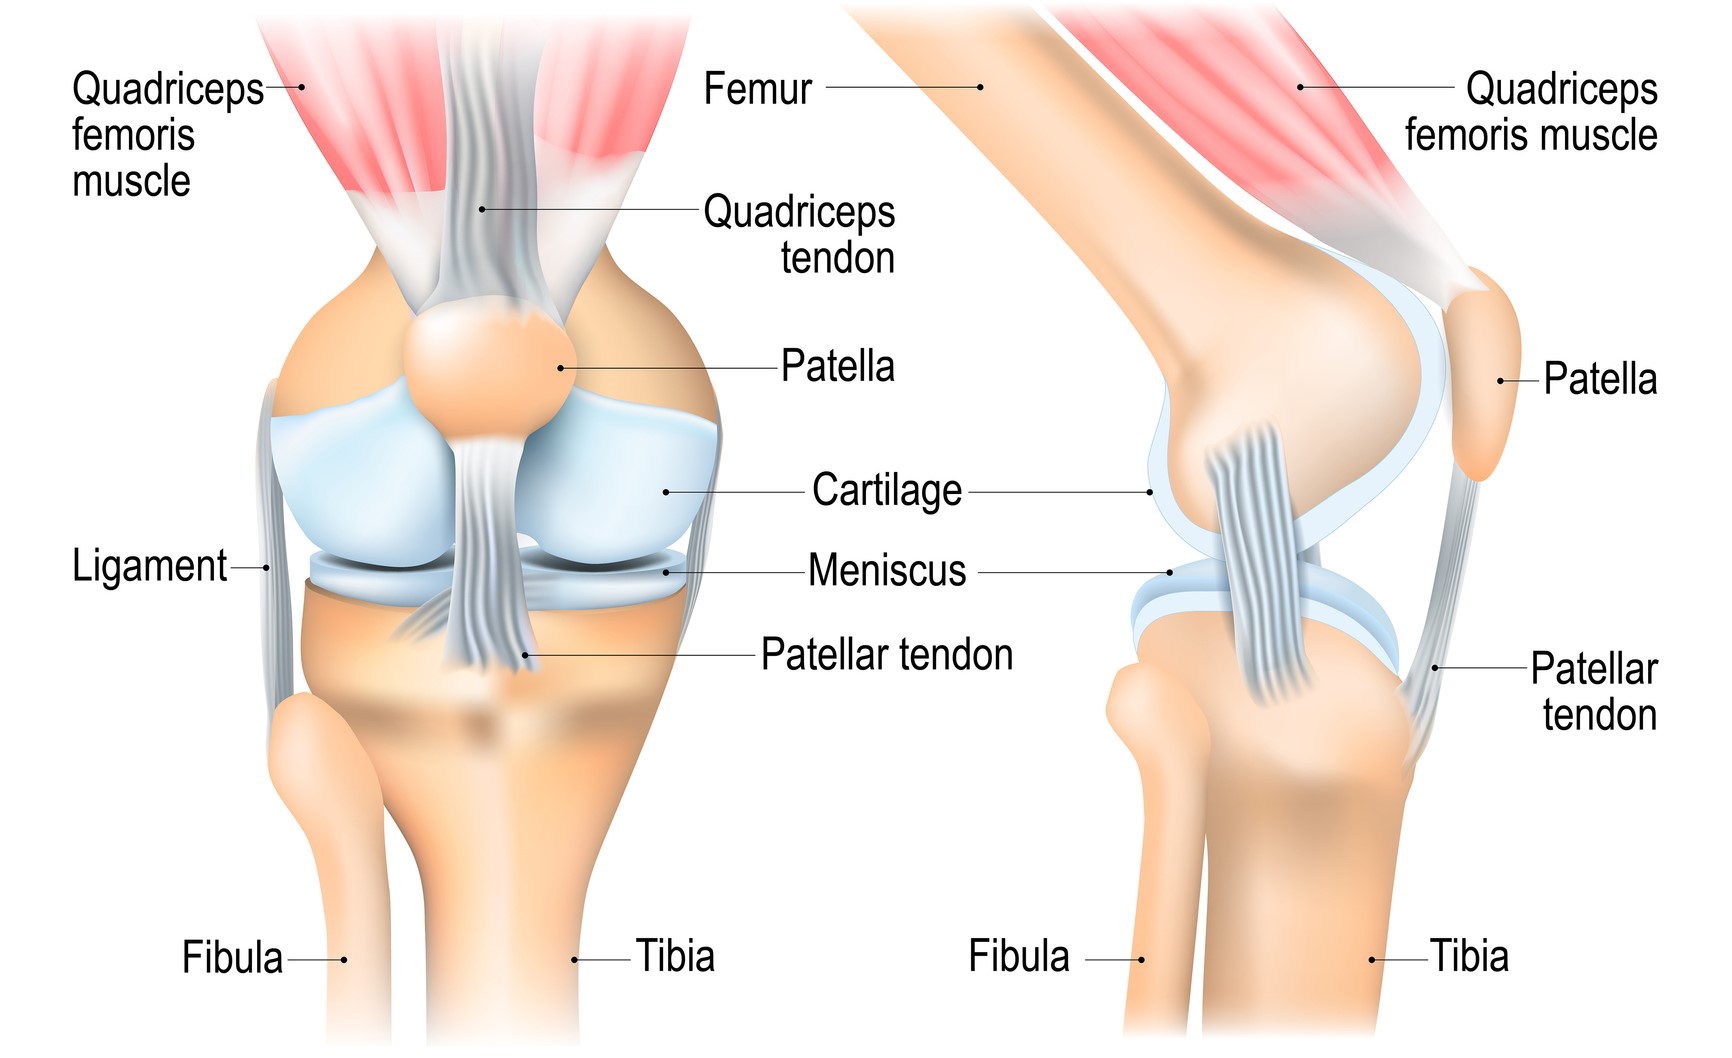

Chondromalacia Explained Causes Symptoms Diagnosis

What Is Chondromalacia Patella Symptoms Causes Diagnosis

Chondromalacia Patella Causes Symptoms Treatment for Knee Pain

Chondromalacia Patella Symptoms Diagnosis Treatment Pantai

What is chondromalacia patella or soft knee patella

Chondromalacia Patella or Patellofemoral Syndrome What s The